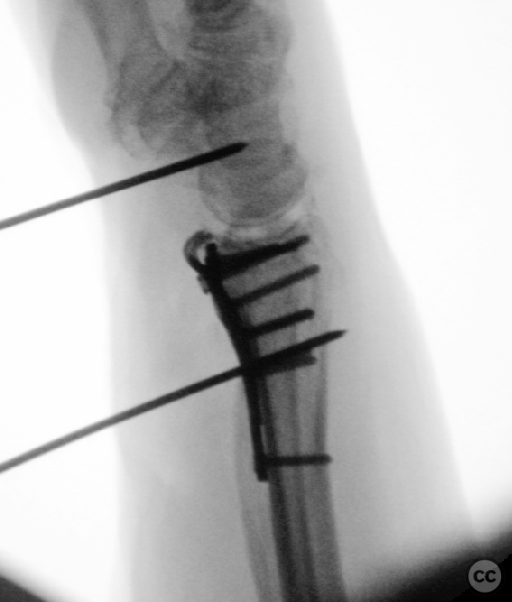

Anatomical surgical approach:  A longitudinal incision was made over the flexor carpi radialis (FCR), zigzagging over the wrist crease. Subcutaneous dissection and incision of the FCR tendon sheath were performed, followed by transection of musculus pronator quadratus fibers along the radial border of the distal FCR. The FCR tendon was retracted ulnarly, and the antebrachial fascia incised. Musculus flexor pollicis longus was identified and retracted ulnarly. The pronator quadratus was incised along its radial border and the watershed line, then elevated subperiosteally to expose the distal radius. Extended distal release of the FCR allowed wide exposure of the ulnar aspect of the lunate facet and volar lip. The flipped volar ulnar fragment was de-rotated and provisionally fixed with a Kirschner wire. Ligamentotaxis for radial styloid reduction was achieved using Kirschner wires in the scaphoid and distal radius, with a wire spreader applied for distraction. Provisional fixation was achieved with multiple Kirschner wires. A mini-fragment T-plate, cut and shaped as a hook plate, was applied to the volar ulnar lip fragment, fixed with bicortical screws, and used to engage dorsal fragments. The radial styloid was addressed with a contoured T-plate, similarly fixed with bicortical locking screws. Final multiplanar fluoroscopy confirmed anatomical reduction and hardware placement.

The flipped volar ulnar articular margin fragment was irreducible by closed means due to capsular attachment and required direct open de-rotation and fixation. The impaction and proximal displacement of the radial styloid fragments were challenging due to persistent traction from musculus brachioradialis and scaphoid pressure; ligamentotaxis using Kirschner wire spreader over the scaphoid facilitated reduction. Fragment-specific fixation was necessary: a custom-shaped hook plate for the volar ulnar lip fragment provided stable fixation and prevented dorsal instability, while a separate T-plate addressed the radial styloid. Bicortical locking screws were used to secure both plates, with some screws engaging dorsal fragments from the volar side. Careful adaptation of pronator quadratus over hardware minimized risk of musculus flexor pollicis longus irritation. Additional suture stabilization of radiocarpal ligaments to pronator quadratus provided secondary ligamnetal support.

Orthopaedic implants used:   - 1.0 mm Kirschner wire (provisional fixation) - 1.8 mm Kirschner wire (scaphoid traction) - 2.0 mm Stryker mini fragment T-plate (cut/shaped as hook plate) - 2.4 mm T-plate (radial styloid fixation)